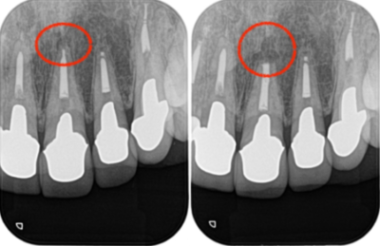

当院にて詳しく診査を行ったところ、左上1番の歯に根尖性歯周炎(虫歯や歯髄炎が進行し、歯の根の先周辺の歯周組織に炎症が生じた状態)が確認されました。

この炎症が、患者様が感じていた違和感の主な原因であると診断しました。

レントゲン画像がこちらになります。

治療前レントゲン画像①|【症例】セラミック治療後に発症した根尖性歯周炎に対する歯根端切除術|目白マリア歯科

治療前レントゲン画像②|【症例】セラミック治療後に発症した根尖性歯周炎に対する歯根端切除術|目白マリア歯科